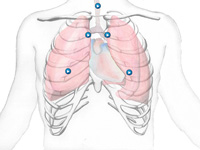

OMARC: An Online Multimedia Application for the Assessment of Respiratory Conditions

OMARC is a multimedia application designed to support the training of health care providers in the identification of common lung sounds heard in a patient's thorax as part of a health assessment session or group of sessions. The main goal of OMARC is to effectively help health-care students and professionals to become familiar with lung sounds that might be heard during the assessment of respiratory conditions. OMARC was developed using an online platform to facilitate access to users in remote locations and is designed in a way that is easy to use and accessible to students and practitioners over the internet.

(accepted manuscript; online article @ IJMI; reference).